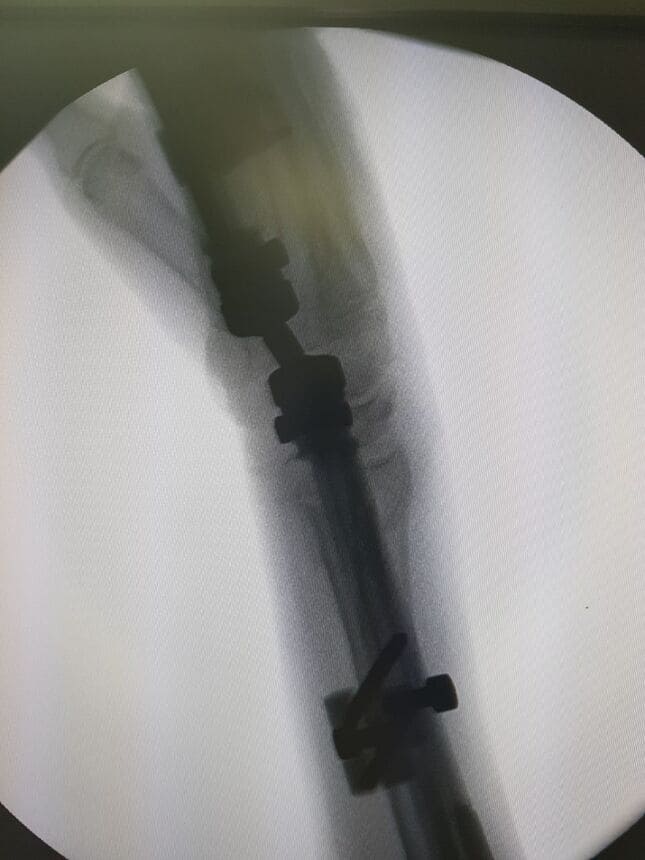

Clavo de fémur